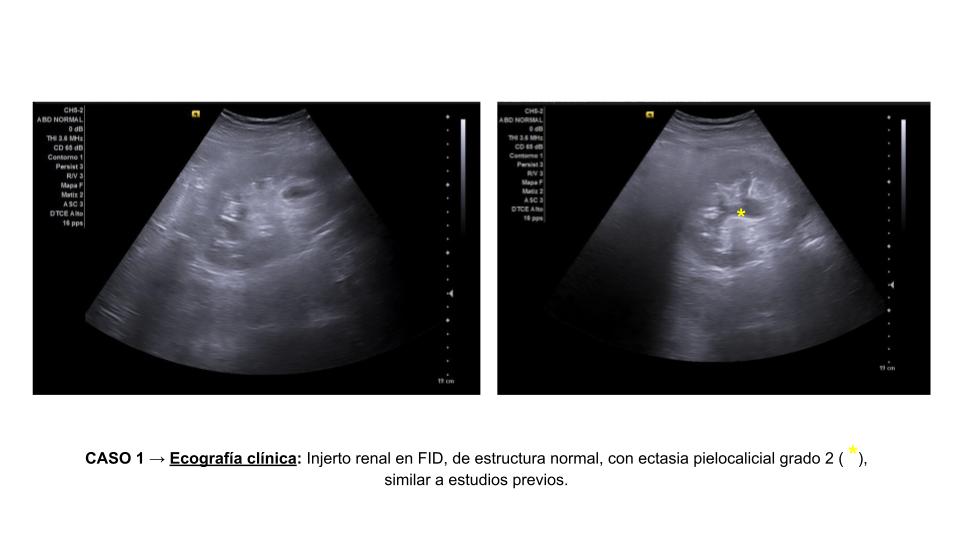

Se presentan dos casos clínicos sometidos a trasplante renal.

Ambos pacientes acuden a su seguimiento habitual.

Descripción de los hallazgos ecográficos y las imágenes más relevantes para la resolución del caso

Diagnóstico: Ectasia pielocalicial en injerto renal.

Estos casos tienen en común: dilatación pielocalicial en los injertos renales postrasplante.